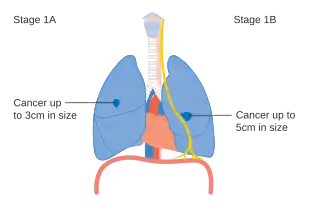

- Diagrams of main features of staging

-

Stage IA and IB lung cancer -

Stage IIA lung cancer -

Stage IIB lung cancer -

One option for stage IIB lung cancer, with T2b; but if tumor is within 2 cm of the carina, this is stage 3 -

Stage IIIA lung cancer -

Stage IIIA lung cancer, if there is one feature from the list on each side -

Stage IIIB lung cancer -

Stage IV lung cancer